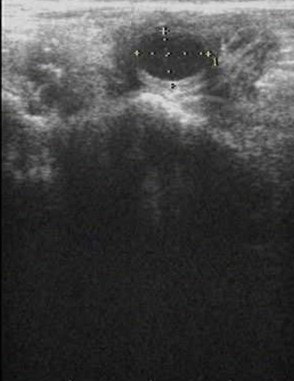

在對腱鞘囊腫的患者進(jìn)行超聲檢查時,可能會有如下的表現(xiàn): 1、首先會發(fā)現(xiàn)局部有一個囊性的病變區(qū)域,而且跟周圍組織的界限非常的明顯,在其界限或者是邊緣的部位有一些高回聲的信號,提示此處存在囊壁。 2、在囊變區(qū)域的中心會有一系列均勻的低回聲,提示在囊變的內(nèi)部充填著液體。 3、在對此處的囊腫進(jìn)行適度擠壓的時候,可以發(fā)現(xiàn)此處的囊變并沒有明顯的減小或者是其內(nèi)部的液體有轉(zhuǎn)移的情況。 對于出現(xiàn)了上述表現(xiàn)的患者,基本上就可以使用超聲來判斷患者存在腱鞘囊腫。